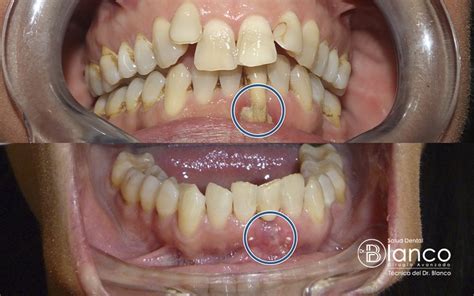

- Cirugía plástica mucogingival o injerto de encía: Con esta técnica tomamos un fragmento de mucosa de tu paladar y lo colocamos sobre el sitio donde has perdido encía, recubriendo las raíces dentarias expuestas. Con esto buscamos regenerar el tejido faltante.

- Estiramiento de encía: Esta técnica, también llamada «colgajo movilizado coronalmente» lo podemos realizar si tienes conservadas tus papilas interdentarias, que son la porción triangular de encía que hay entre diente y diente.